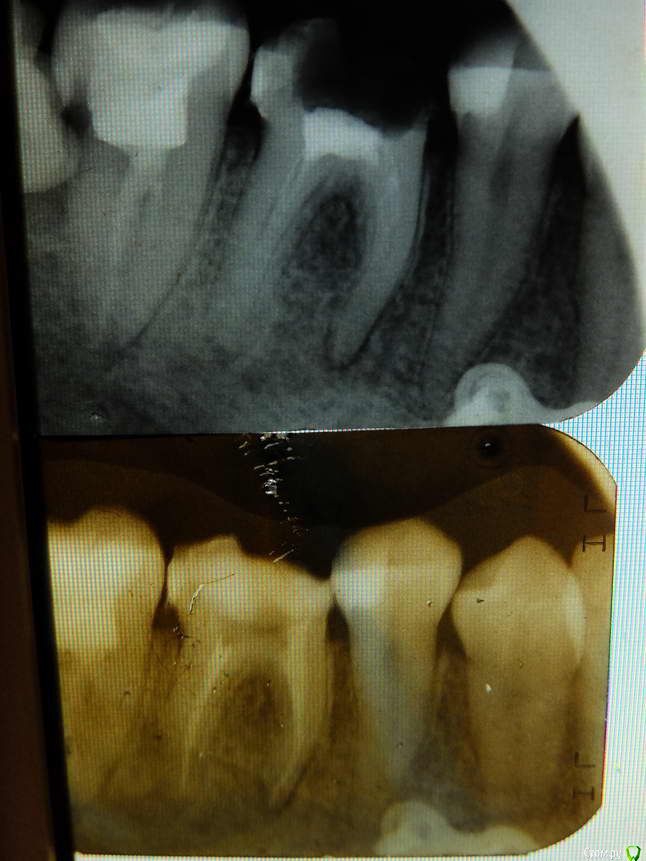

lejeboka Опубликовано 10 мая, 2018 Поделиться Опубликовано 10 мая, 2018 (изменено) Добрый день На днях сходил к стоматологу на контрольных осмотр и проф гигиену. Лечусь у нее с 2010 года, в общем доверяю. Результат расстроил.6-й слева снизу – на удаление.Зуб был депульпирован в 1990-м, в райполиклинике, спустя 2-3 года поставил коронку там-же. Успешно проходил с ней 17 лет, потом решил поменять на металлокерамику. Врач-ортопед ставить коронку отказался, т.к. были изменения на корнях.Переделали каналы. Спустя 6 лет – киста, культевую вкладку удалить нельзя, зуб на удаление. https://cloud.mail.ru/public/JuP9/LF2BUBPsG https://cloud.mail.ru/public/9mas/cnXZ2Ra6JСедьмой справа сверху – необходимо ставить коронку, т.к. пломба выпала, и качественно ее поставить нельзя. Зуб был депульпирован в 2011-2012 году лечащим врачом. Но нужно переделать один из каналов. https://cloud.mail.ru/public/7fhp/wFFS5S6S4 Седьмой снизу (рентгена нет) , справа, поставлена коронка 6 лет назад коронку надо менять, т.к. десна опустилась. Вопрос 1: нормально ли это, что спустя 5-7 лет после депульпирования нужно переделывать каналы, а после ревизии каналов зуб идет на удаление? Каналы были запломбированы хорошо, в чем тогда проблема, в стерильности при работе?Прошу прощения перед доктором, если она вдруг читает этот форум.Еще у нас был пропущеный канал на одном из зубов и киста. В след четверг записался на удаление левой нижней шестерки.Вопрос 2, извините если слишком ламерский. Как я понимаю, при удалении зуба при планах на последующую имплантацию иногда в лунку добавляют какой-то материал для того, что бы кости было больше. Это нужно обсуждать с доктором перед удалением? Доктору нужно будет передать рентгеновский снимок? Вопрос 3: правильно я понимаю, что на корнях 7-ки снизу слева то-же есть проблемы? Изменено 10 мая, 2018 пользователем lejeboka Ссылка на комментарий